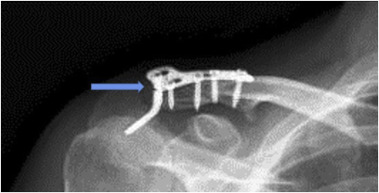

Fig. 1

Fig. 1.

(a) Anteroposterior radiograph of the right shoulder of a 33-year-old man who sustained a Neer type 2 distal clavicle fracture. (b) Early postoperative radiograph of the internal fixation using a hook plate with six holes. (c) Bony union was achieved after 12 weeks but the radiograph shows the subacromial osteolysis (blue arrows) around the tip of the hook of the same patient before implant removal (For interpretation of the references to colour in this figure legend, the reader is referred to the web version of this article).